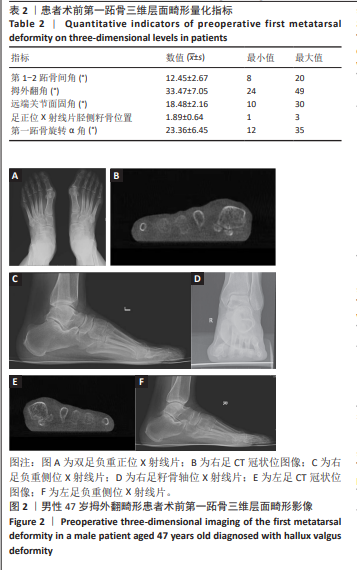

方法:选择2022年1-12月衡水市人民医院手足外科收治的拇外翻畸形患者100例(足),均行Scarf截骨矫形治疗。治疗前、治疗后6个月拍摄负重位足部正侧位X射线片及模拟负重位CT片,观察测量第1-2跖骨间角、足正位X射线片胫侧籽骨位置、第一跖骨旋转α角、远端关节面固角、拇外翻角,分析第一跖骨三维层面畸形量化指标之间的相关性,比较治疗前、治疗后6个月畸形量化指标及美国足踝外科协会评分的差异,并分析治疗后6个月第一跖骨三维层面畸形量化指标与美国足踝外科协会评分的相关性,评估畸形量化指标预测功能预后的效能。

METHODS: One hundred patients (feet) with hallux valgus deformity in Department of Hand and Foot Surgery, Hengshui People’s Hospital were selected from January to December 2022, and all of them underwent Scarf osteotomy and orthopedic surgery. Preoperative and 6-month postoperative orthopedic X-rays of the foot in weight-bearing position and simulated weight-bearing position CT films were taken to observe and measure the intermetatarsal angle of the first and second metatarsal bones, tibial lateral sesamoid bone position on orthopedic X-rays of the foot, first metatarsal rotational α-angle, distal articular facet fixation angle, and the angle of the hallux valgus. The correlation of deformity quantifiers at the three-dimensional level of the first metatarsal bone was analyzed, and deformity quantifiers and American Orthopaedic Foot & Ankle Society scores were compared preoperatively and at 6 months postoperatively. The correlation between the quantitative index of deformity at the three-dimensional level of the first metatarsal bone and the American Orthopaedic Foot & Ankle Society score 6 months after treatment was analyzed to evaluate the efficacy of the quantitative indicators of the deformity in predicting functional prognosis.